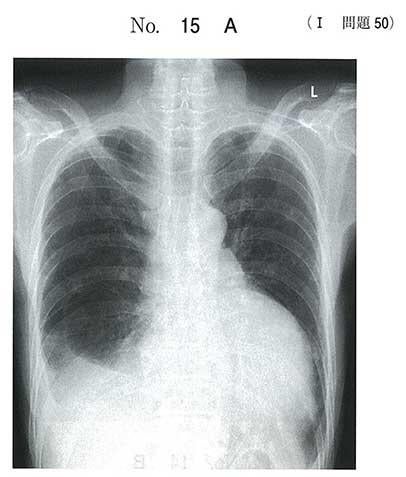

慢性経過の方ですねー。

こういうのは以外と緊急性がないかもですねー。

画像はすっごく派手で、びっくりします!

これって、何mL位溜まってるんでしょうかねぇ…